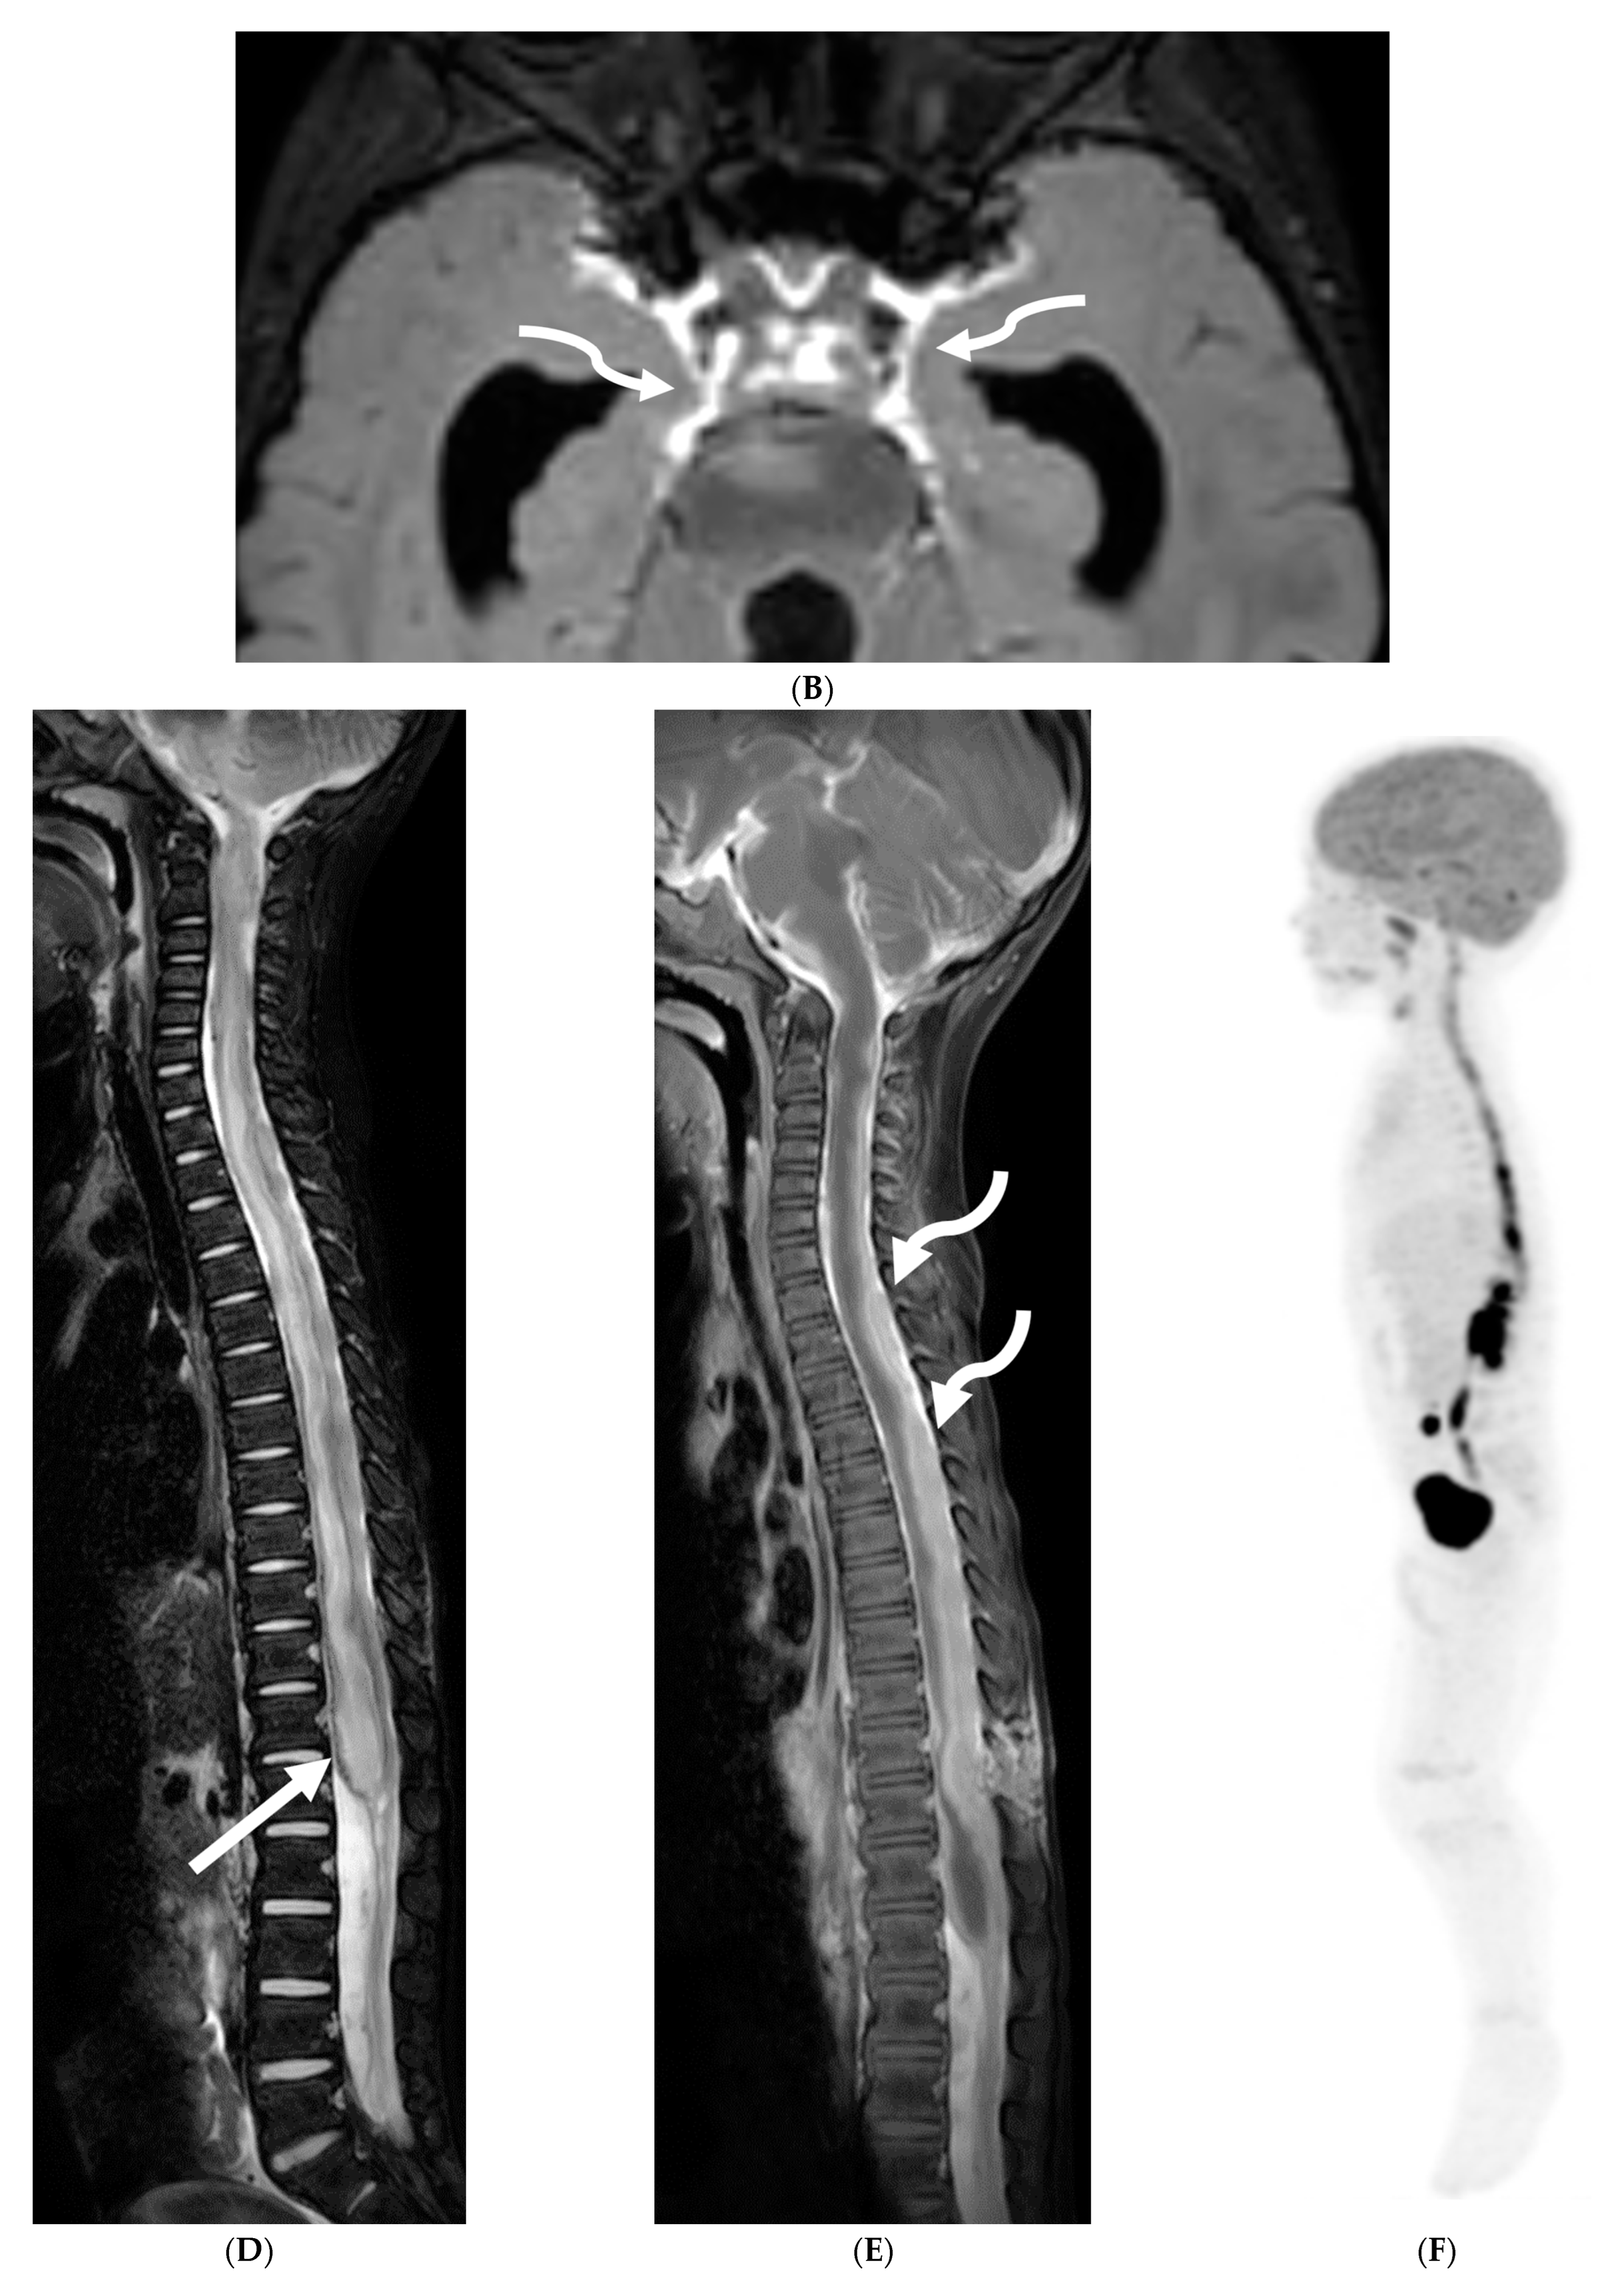

ALK-positive histiocytosis (APH) is a rare, non-Langerhans cell histiocytosis that can involve the nervous system, including the meninges. While the disease is often seen in infants and young children, it can occur at any age [68]. Neurologic involvement usually presents as seizures, ataxia, headaches, and vomiting [69]. Imaging findings on CT include iso-dense or slightly hyperdense nodules/masses [70]. On MRI, lesions demonstrate isointense or slightly hypointense signals on T1-weighted, isointense or hypointense signals on T2-weighted, with moderate homogeneous focal or smooth ring enhancement [71]. Meningeal enhancement (Figure 10F) can appear segmental and be particularly prominent along the cauda equina [71]. Restricted diffusion is also commonly seen (Figure 10 and Figure 11) [69].

Figure 10.

Axial T2 (A), sagittal T1 post contrast (B), Sagittal T2 (C,E) and sagittal T1 post contrast (D,F): 20-month-old boy with 2 months of losing developmental milestones and 1 month of emesis, fatigue and dehydration. Ventriculomegaly with transependymal fluid is noted (black arrows). There is posterior fossa leptomeningeal nodular enhancement extending into the upper cervical spine (curved white arrows). Extensive nodular enhancement along spinal cord (dashed white arrows) with cord edema demonstrated in the entire cord (white arrows).

Figure 11.

3 weeks follow up: Post contrast sag T1 (A) and axial FLAIR (B), Axial T2 (C), sagittal T2 (D), Post contrast sagittal T1 (E) and PET/CT (F): Leptomeningeal nodular enhancement along posterior fossa, suprasellar and spinal cord (curved arrows) has significantly increased. There is also new/increased signal abnormality in the brain stem and cord (white arrows). Hypermetabolic spine disease is demonstrated on PET/CT. No osseous involvement is identified on the PET scan. Pathology: Diffuse CNS ALK (Anaplastic Lymphoma Kinase)-Positive Histiocytosis. Bone marrow biopsies, US abdomen and skeletal survey negative for extracranial/extraspinal disseminated disease.

Differentiating APH from other meningeal diseases can be challenging. The most important imaging differential is meningioma. Meningiomas are typically well-circumscribed, dural-based lesions that enhance intensely and homogeneously. Meningiomas often demonstrate a “dural tail”—a thin, linear enhancement extending from the main tumor mass along the dura mater [71]. Another important differential is juvenile xanthogranuloma (JXG), which can also involve the meninges. JXG lesions are typically well-defined, enhancing nodules that are often located near the ventricles or meninges [71]. Ultimately, a definitive diagnosis of APH requires histopathologic and molecular testing, which demonstrates the presence of ALK rearrangement, typically a KIF5B-ALK fusion [72].